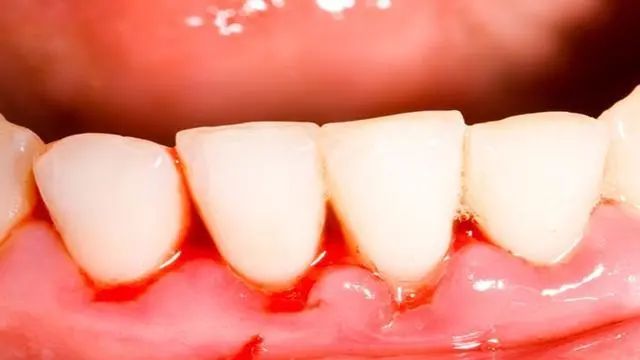

牙周炎 症状1:牙龈红肿出血

牙周炎主要表现为牙龈红肿、出血,不仅在刷牙时出血,有时在说话或咬硬物时也要出血,有时可自发出血。

牙龈颜色暗红,由于水肿显得比较光亮。健康的牙龈,即使用力刷牙或轻探龈沟均不引起出血。

而在初期和早期龈炎阶段,轻探龈沟即可出血。它比牙龈颜色的改变出现得早些,而且也较客观。故探诊出血,可作为诊断牙龈有无炎症的重要手段。